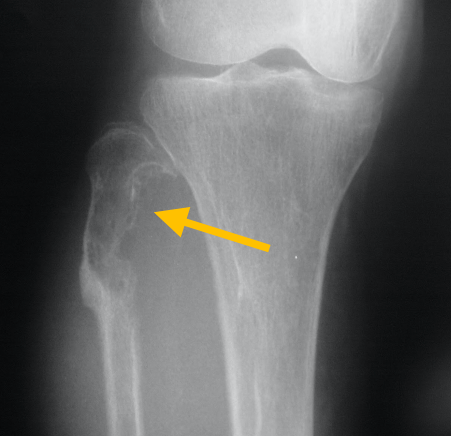

Radiographic imaging is used to help form a diagnosis. These include X-Ray, MRI, CT and Bone Scans.